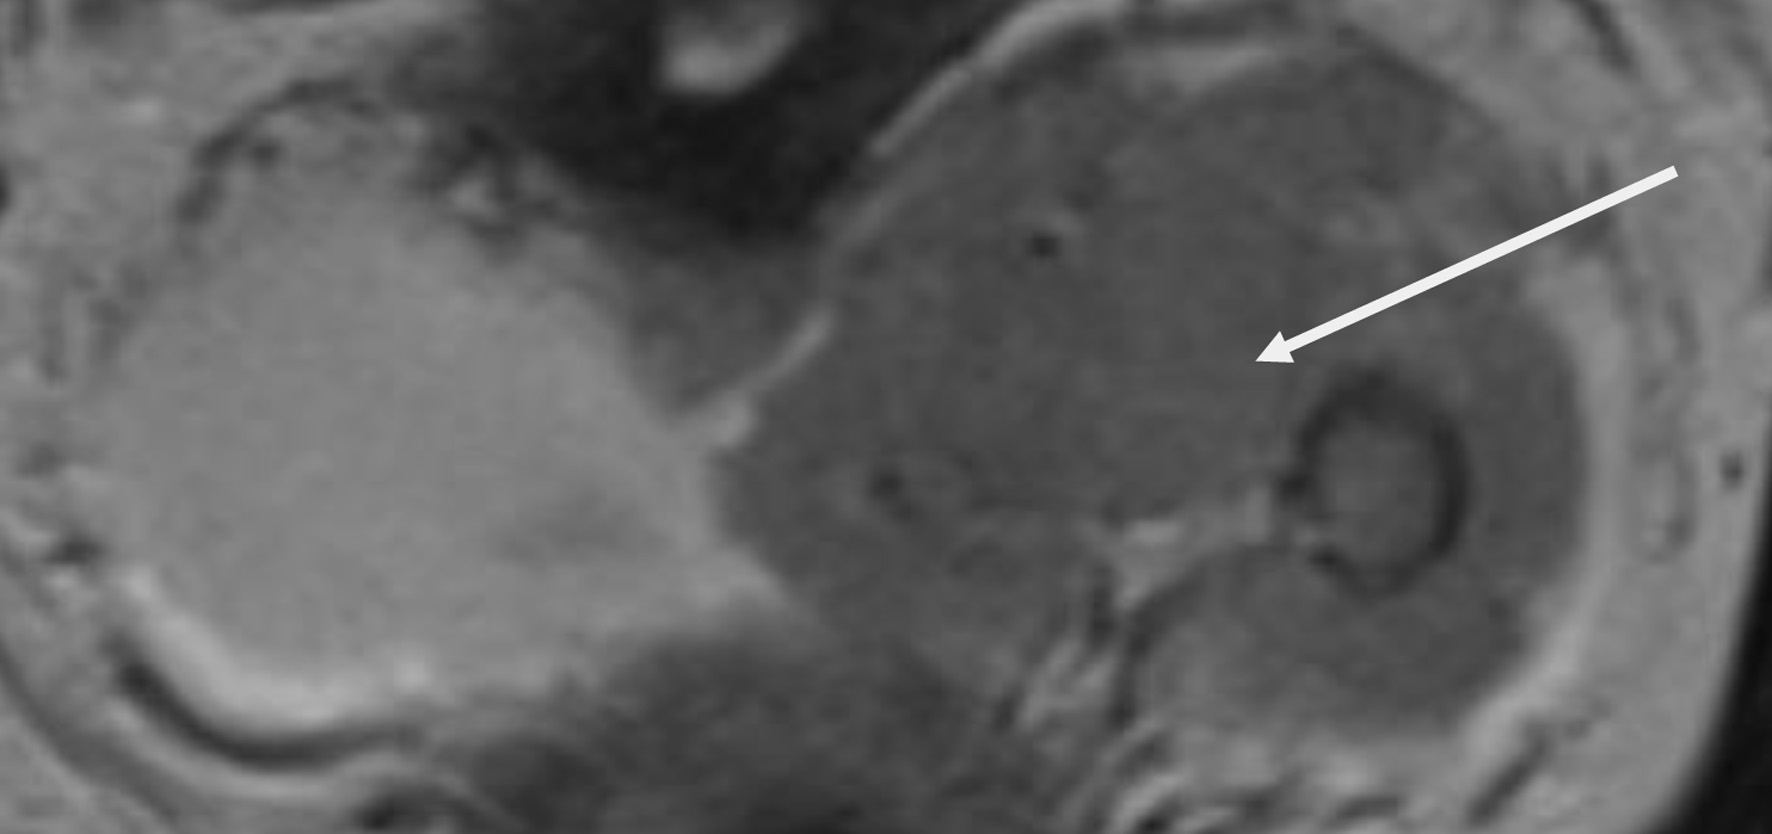

The surgical procedure involved a combined laparoscopic and open approach that included right radical nephroureterectomy, cystectomy, and total hysterectomy with bilateral salpinges-oophorectomy. The resected organs were sent in their entirety to the Department of Pathology, without additional dissection, in accordance with departmental protocol (Figs. 3 and 4). The total operative time was approximately 4.5 h. Throughout the procedure, hemodynamics remained stable, and no arrhythmias, ischemic electrocardiographic changes, or significant hypotensive episodes were observed.

Figure 3. Right radical nephroureterectomy (arrow indicates the ureter).